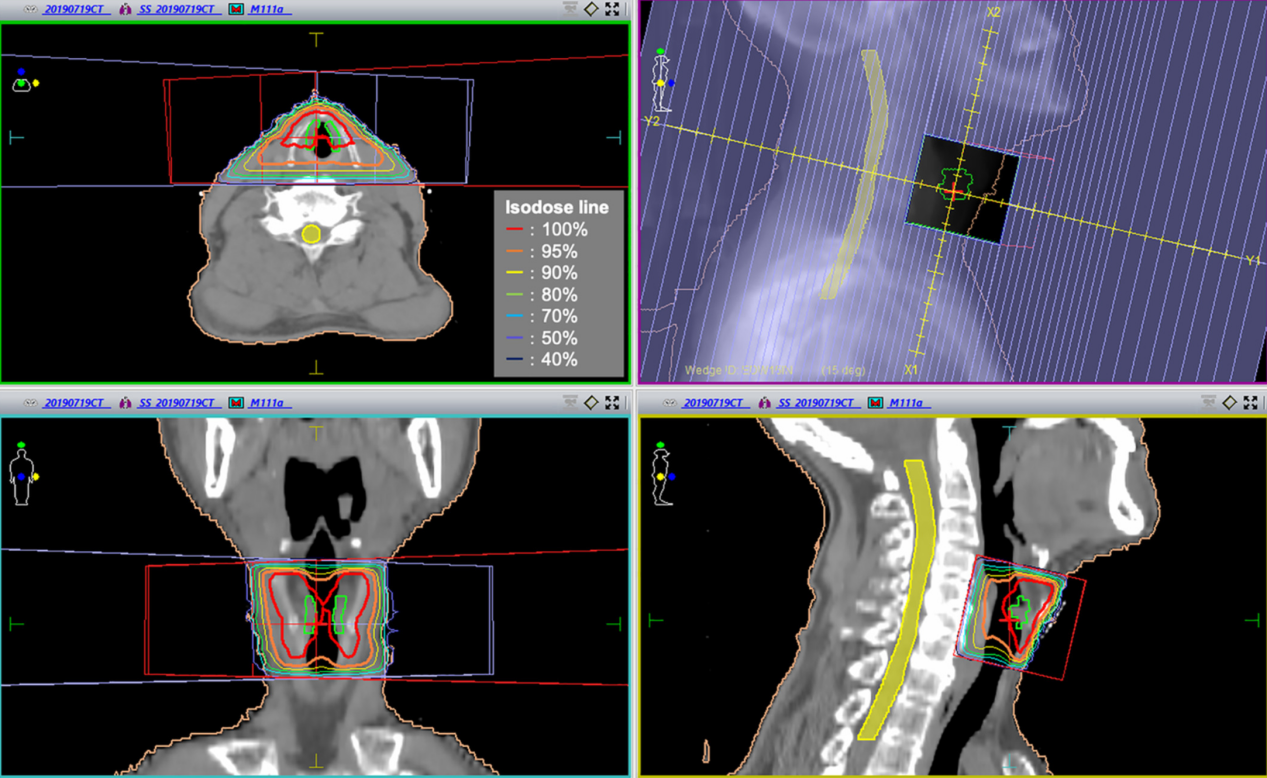

计算机断层扫描(CT)结果显示没有淋巴结或远处转移。患者的临床分期为T1aN0M0,I(TNM分类,第8版)。仅计划了单纯放疗。RT剂量为63 Gy,采用三维常规RT技术和动态楔块,分28个部分输送至喉部。辐射场大小为5.5 × 6 cm,采用传统矩形场(图2)。

图2